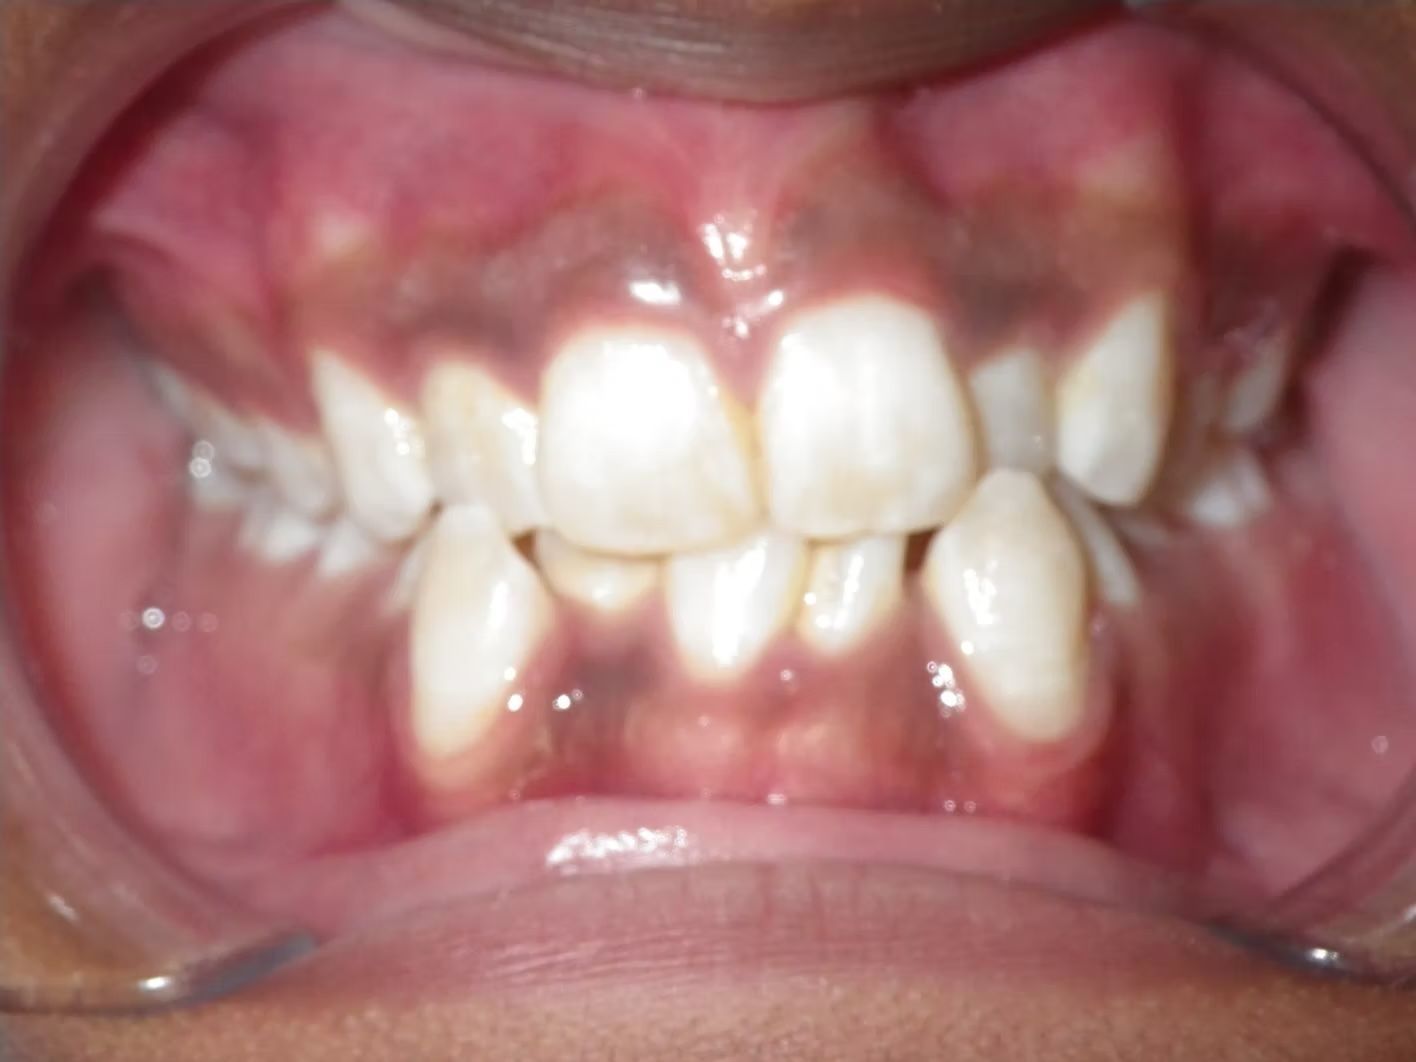

Johntavious

Johntavious didn't like that one of his lower teeth was set behind the rest. He went to many orthodontists who told him to extract the tooth or multiple teeth to correct the alignment. Johntavious and his parents didn't want to go that route and wanted to try to align the teeth without the extraction. Dr. Bret was able to successfully straighten the upper and lower teeth - fit the tooth that was back into the dental arch and make Johntavious and his parents really happy.